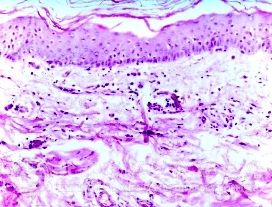

自体过敏性皮炎的影响因素有什么?现在是自体过敏性皮炎的高发期,有很多人被自体过敏性皮炎所困扰着,但由于对自体过敏性皮炎不是清楚,当出现皮炎时没能采取正确的措施,较终导致自体过敏性皮炎病情发展严重,从而增加自体过敏性皮炎治疗难度。那么自体过敏性皮炎的影响因素有什么呢?为此北京京城皮肤医院就自体过敏性皮炎的影响因素进行介绍,让我们来看看吧。

自体过敏性皮炎的发生、发展与各种因素有关。由于个体差异,不同个体或同一个体的不同时期都有可能出现差异。除饮食方面的因素外,吸入物,如花粉、尘、螨及体表的细菌、真菌感染、生活环境的改变以及所接触到的各种物质,都有可能成为引起皮炎的常见外部原因。